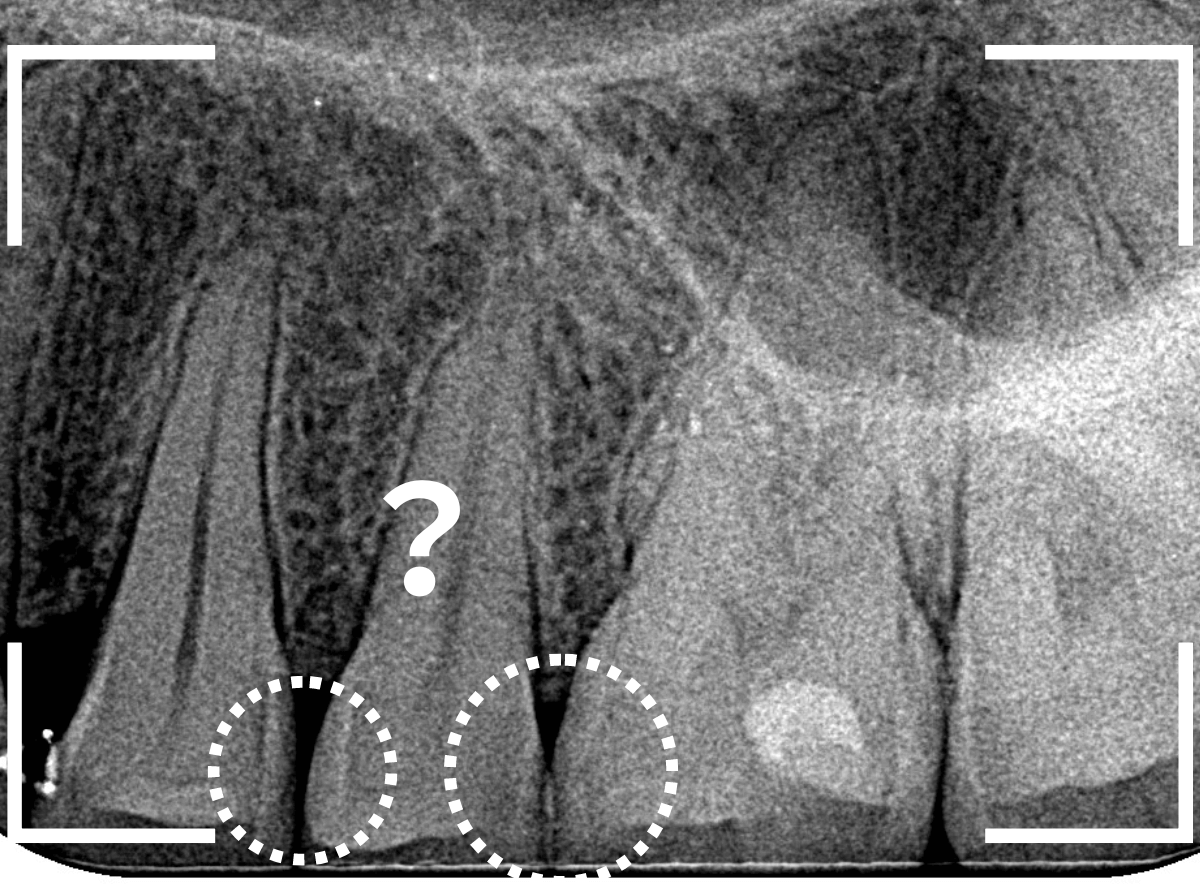

Case.11 治療をするべきか悩むケース

日々、診療をしていると、治療をすべきか、経過観察すべきか悩むケースによく当たります。

歯科医によって虫歯の数が違った!という話を聞きますが、こんなケースが多いのではないかと思います。

見た目は問題なさそうな所見です。

歯石除去時に黒い点が見つかりました。

見た目だけの小さな点であれば、経過観察でよいかと思うのですが、

- 歯と歯の間(隣接面)→虫歯が進行しやすい場所

- 黒い点がひっかかる→虫歯が進行している可能性

という点が気になります。

何はともあれ、レントゲン写真で確認します。

黒い点の前後がボヤっと黒っぽく写ります。

何かありそうにも何もなさそうにも見える、あいまいな写り方です。

あとは、患者さんに説明して削って中を調べていくしかありません。

患者さんの同意を得られましたので、慎重に削って中を見てみると、手前の歯からも虫歯が見えてきました。

手前の歯は中の方まで虫歯が進行しているのがわかります。

最終的には、元々つまっていたレジンやインレーを外して、しっかり中を調べて治療する事になりました。

すると、その後ろの大臼歯のレジン部にも虫歯が見つかりました。

虫歯がより深く進行する前に処置できてよかったかと思います。